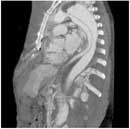

Сканировать большие объемы еще быстрее.

Volume Zoom дает Вам возможность объемного сканирования до 80 мм/секунду, необходимую при обследовании пациентов с травмами, исследовании периферических сосудов и аорты.